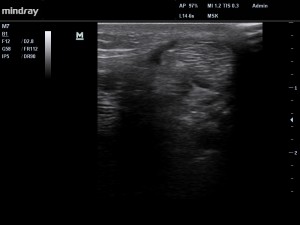

Fig4. Electrolyse (au moyen d’une petite aiguille d’acupuncture) écho-guidée du paratendon.

Le traitement a d’abord été fonctionnel, afin de réduire les contraintes transmises par la fascia crural au para-tendon, puis nous avons réalisé une approche écho-guidée de fenestration/électrolyse  (Fig 4) afin de limiter les phénomène d’adhérence et de retrouver une mécanique tendineuse normale.

Fig 5. Patient asymptomatique, l’échographie retrouve une diminution de l’épaississement du paratendon.

Le patient est redevenu asymptomatique après 3 ou 4 sessions (Fig 5) et a repris ses entrainements. L’utilisation des ondes de choc comme traitement initial dans ce cas précis, n’est probablement pas une bonne indication, car favorisent vraisemblablement la constitution de l’exsudat ainsi que les mécanismes de prolifération cellulaire.